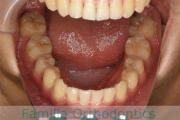

下の歯並びを綺麗にしたいということで来院されました。マウスピース型矯正装置のひとつ、インビザライン/Invisalign®(薬機法および医薬品副作用被害救済制度の対象外)を用いて治療しました。

非抜歯で1年半、20回程度の通院で完了しています。